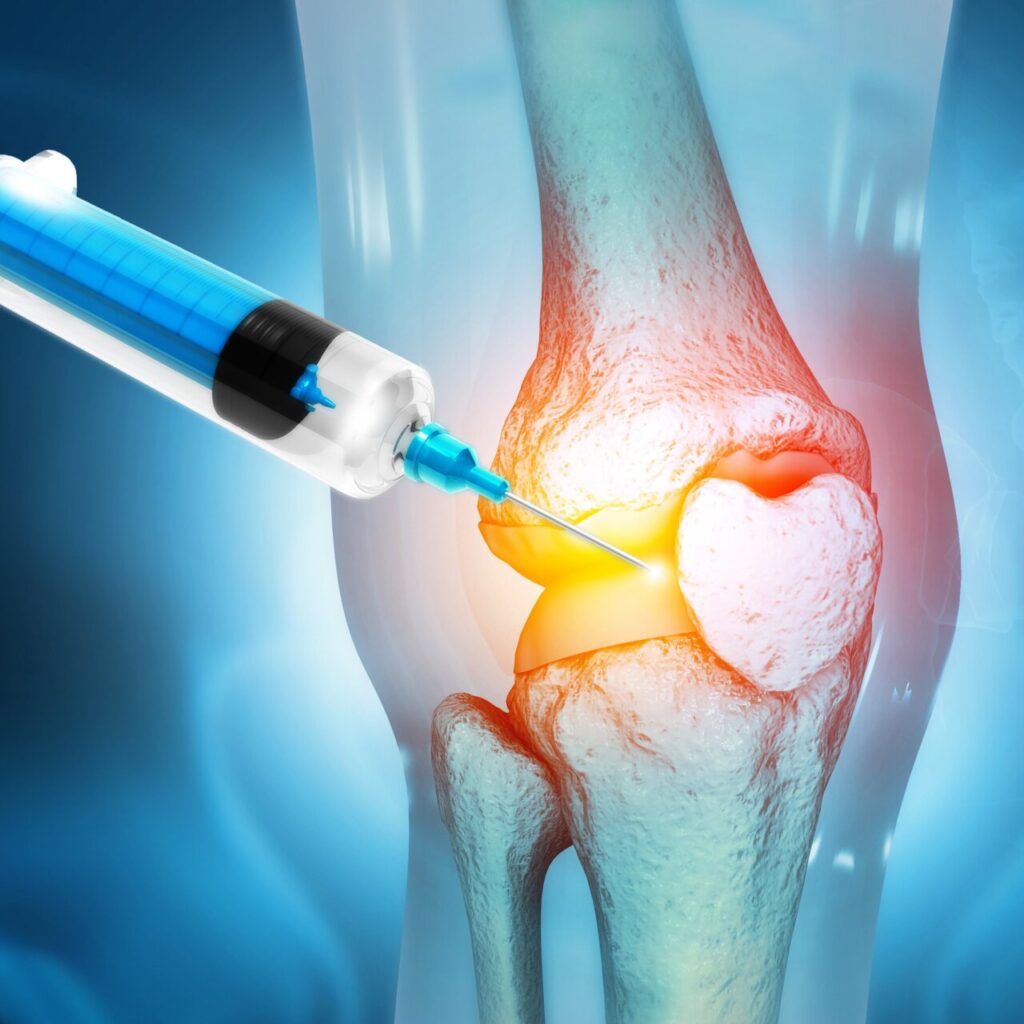

1. PRP Injection (Recommended)

- Ideal for Stage 1 and Stage 2 arthritis

- Helps reduce pain, inflammation, and degeneration

2. PRP Hyaluronic Injection

- Recommended for patients between Stage 2 and 3 arthritis

- Enhances joint lubrication, promoting smoother movement and delaying degeneration

3. PRP for Cartilage Implantation (Micrografting)

- Recommended for Stage 3 or more arthritis

- Also known as micrografting, helps regenerate damaged cartilage

Regenera ATM is a minimally invasive, regenerative medicine treatment for knee pain caused by conditions like osteoarthritis, cartilage damage, or joint degeneration. It uses the patient’s own tissue to promote healing and reduce inflammation.

How Does Regenera ATM Work?

1. Tissue Extraction – A small sample of tissue (usually from behind the ear or abdomen) is taken.

2. Micrografting – The tissue is processed to extract regenerative cells, growth factors, and anti-inflammatory proteins.

3. Injection – The concentrated solution is injected into the affected knee joint* to stimulate repair.